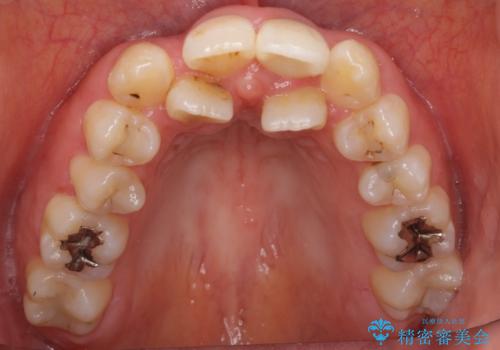

根管治療後、セラミッククラウンによる補綴を行いました。

比較的短い治療期間と自然な仕上がりにご満足頂けました。

ジルコニアクラウン スタンダード